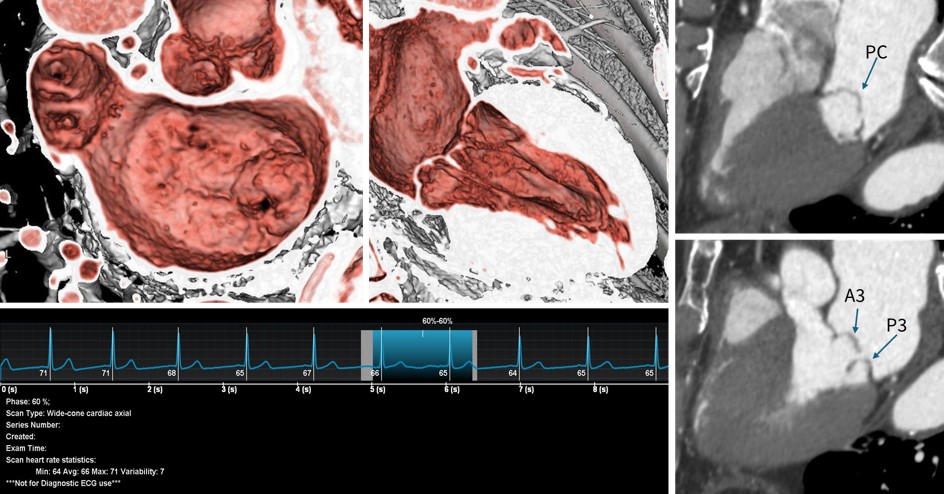

症例紹介

70代 男性 体動時の息切れ,動悸の増強を主訴として近医を受診し心エコーにてSevere MRを指摘され加療目的で当院に紹介.僧帽弁閉鎖不全症の術前精査を目的に造影CTが依頼された.エコーおよびCT画像にて僧帽弁のA3-PCの逸脱を認めた.

Fig.8 僧帽弁閉鎖不全症術前CT症例

撮影条件:70kV 655mA     CTDIvol:14.19mGy

DLP:227.07mGy・cm   Total Exam DLP:1247.36